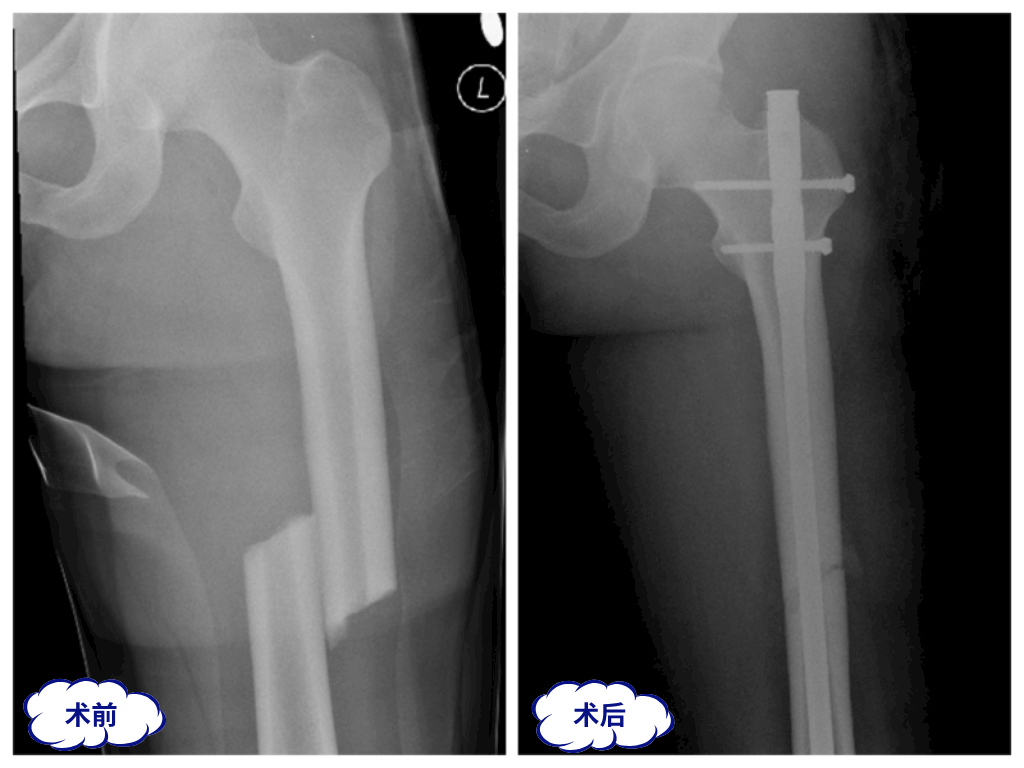

创伤专业